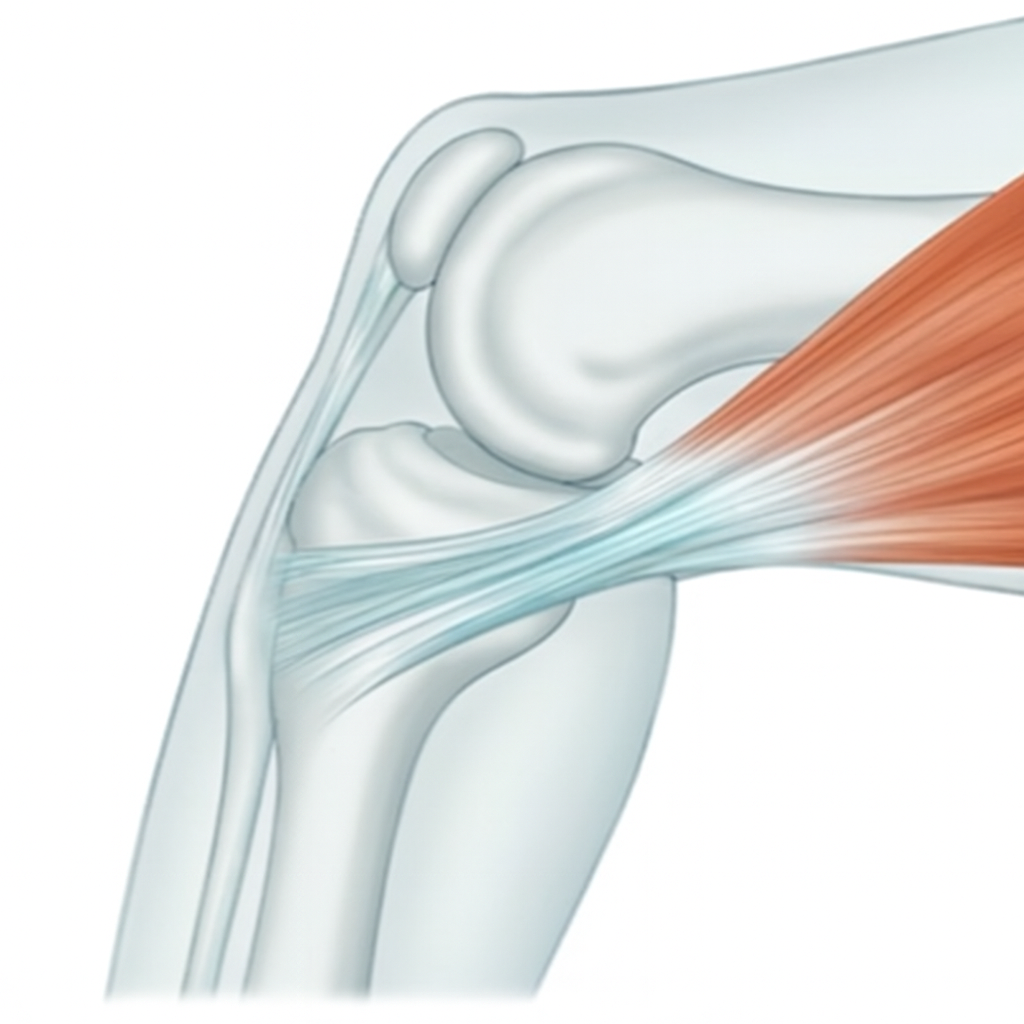

鵞足炎は、膝関節より少し下の内側にある“筋肉の付着部”が炎症を起こしている状態です。

【② 鵞足炎の特徴】

- 膝の関節より少し下の内側

- 押すと“点”で鋭い痛み

- 歩き始めにズキッとする

- ストレッチで痛みが増える

- 画像検査では異常なしと言われやすい

👉 筋肉の付け根(スジの部分)の炎症

筋肉の付け根に負担が集中することで炎症が起こりやすくなります。